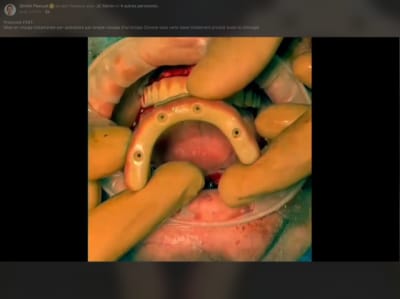

Tu es sur facebook, donc tu as peut être vu sa dernière vidéo ( sur son compte et sur le groupe workflow ).

Sinon : quelques capture d’écran .

Je crois que la, il n’y a plus de doute . Full zircone avec rosenscrew, pas de tibase .

J’ai pas mal de remodelage gingival qui m’empêcherai d’être en prothèse immédiate définitive ( avec des guillemets à « définitif », si tu veux ) . Il utilise une technique de suture suspendue qui évite peut être ce problème . La question sera à poser .

Le principal argument de la mise en en charge immédiate est de pouvoir proposer au patient un temps réduit au maximum pour avoir une prothèse esthétique et fonctionnelle. Les patients qui réunissent le besoin et les moyens sont peu nombreux. Souvent actif, ils veulent pouvoir retrouver une présentation correcte pour reprendre leur travail sans perte de temps. A 6 jours post opératoire comment tu trouves l'aspect esthétique du cas de Dimitri PASCUAL? jeff

.

Tu peux profiter de cette photo pour lire que le bridge n'est pas passif.